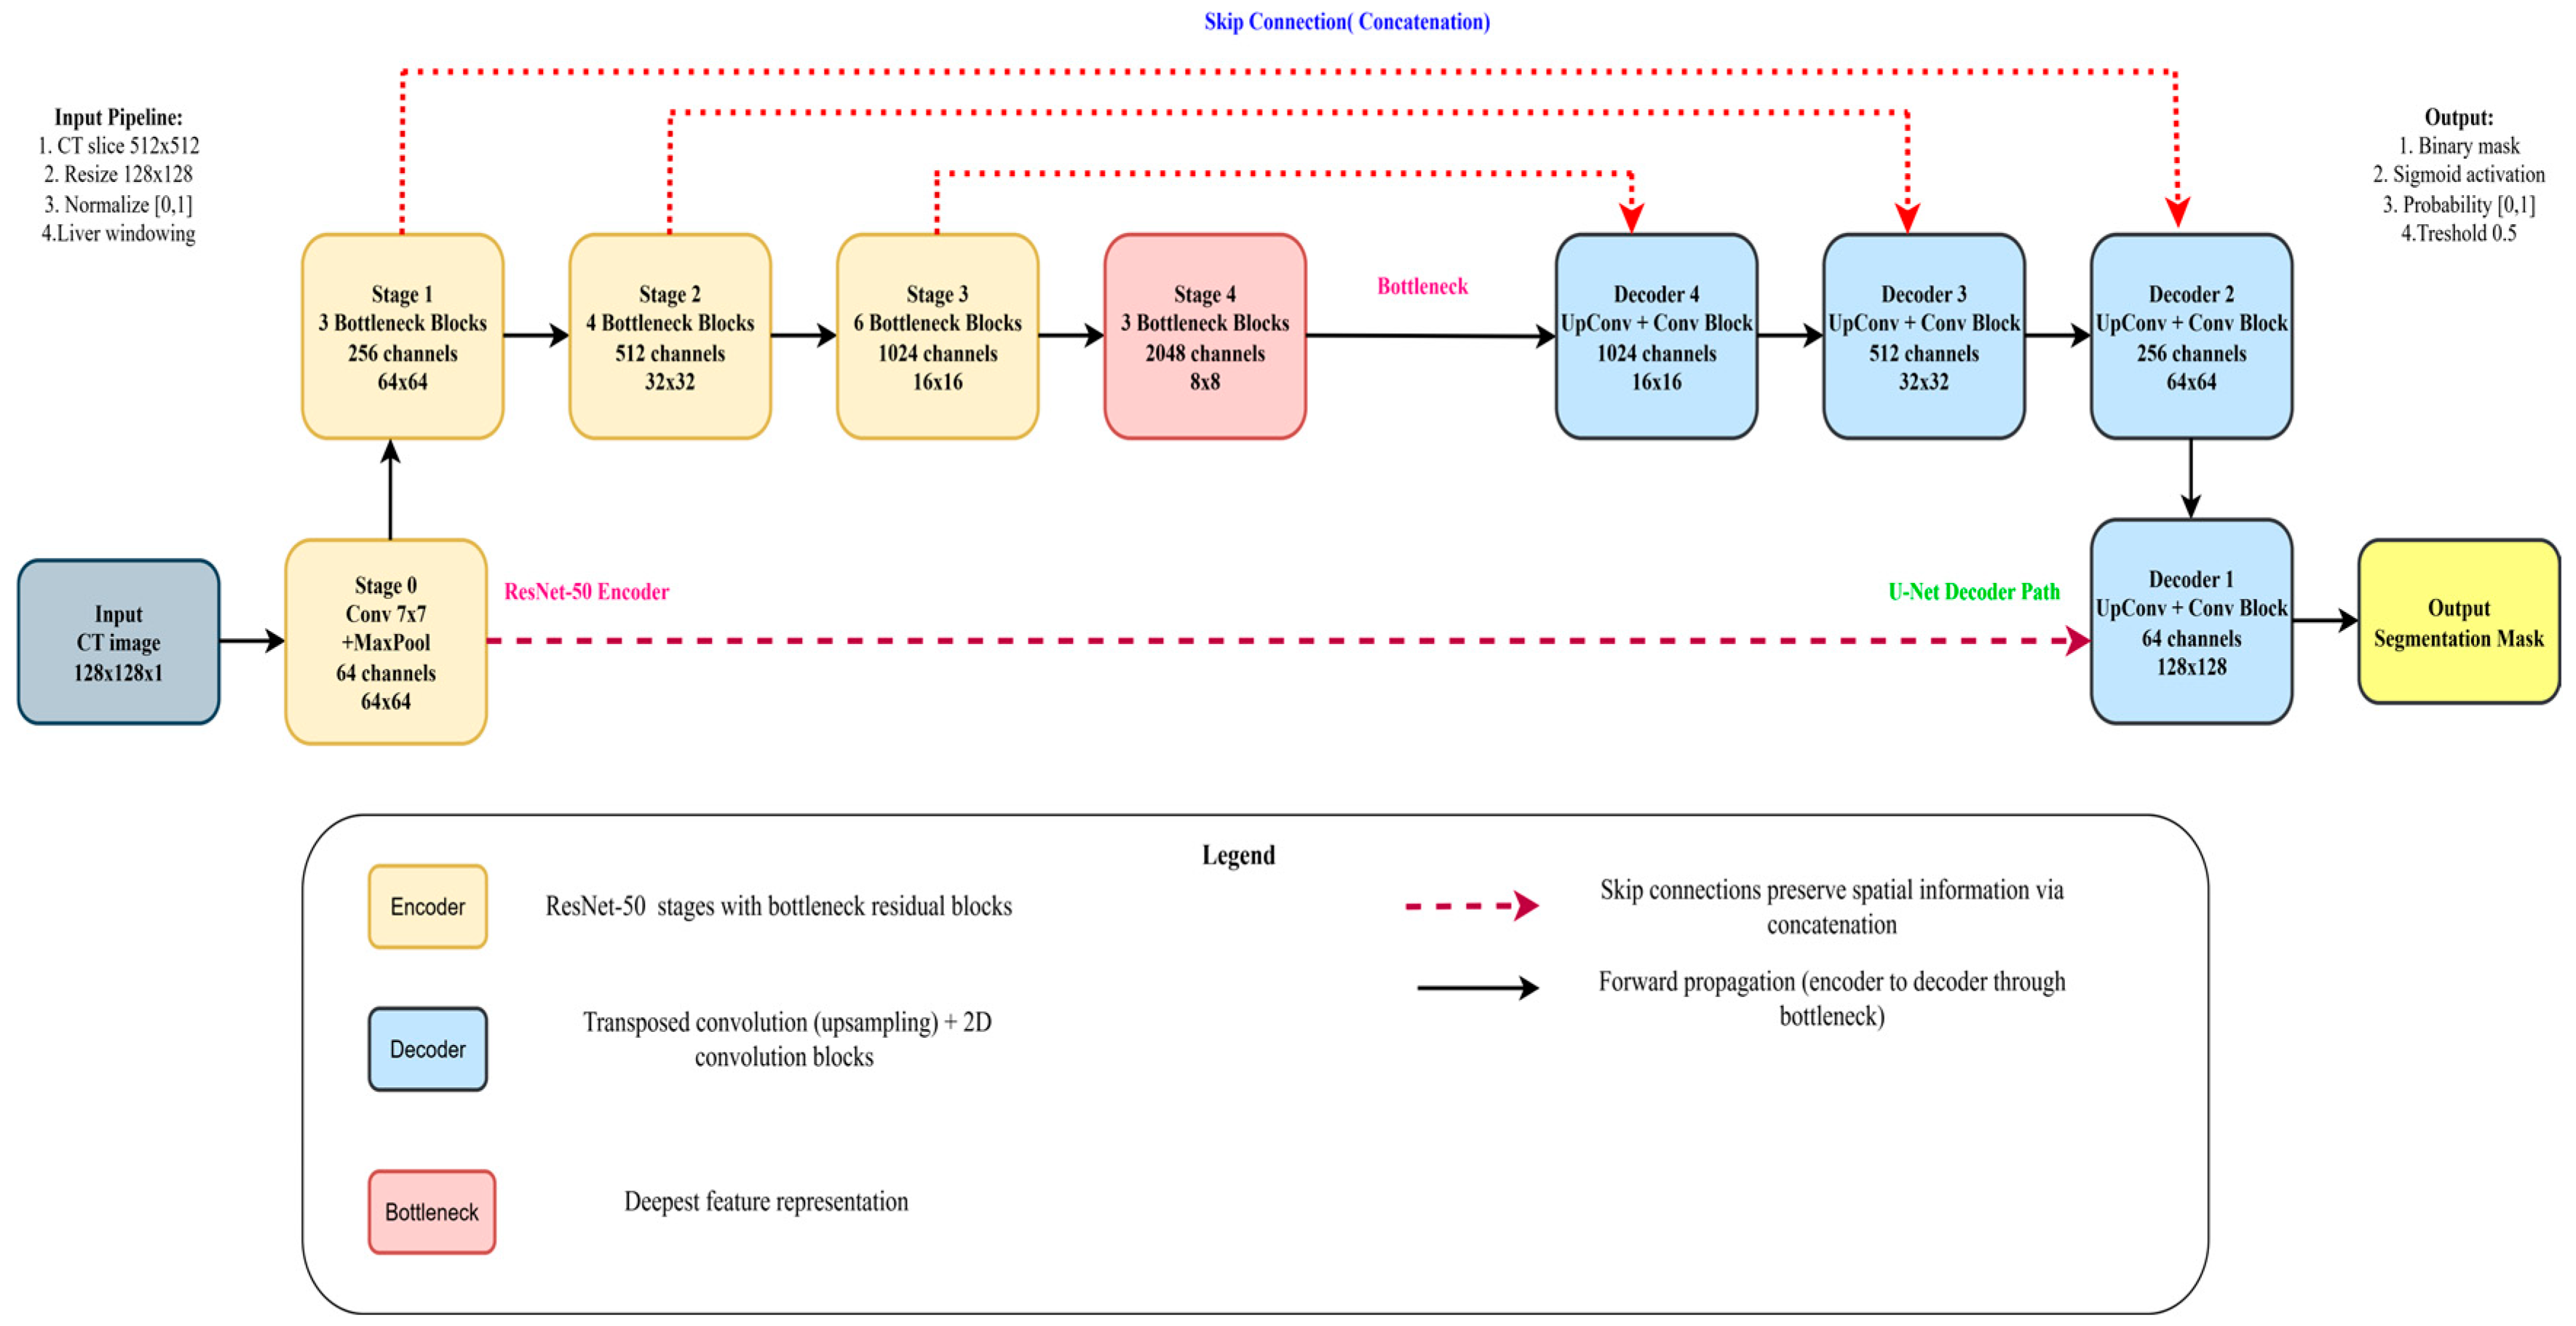

3.3. Based Model Architecture

3.3.1. Pre-Trained Encoder

3.3.2. Model Decoder Path

3.6. ResNet-50 + U-Net

3.6.1. Encoder

3.6.2. Decoder

3.6.3. Bottleneck

3.6.4. ResNet-50 Backbone